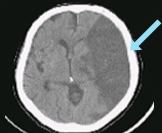

뇌경색

뇌허혈이 뇌경색으로 진행되면 고정된 운동 마비, 감각 장애, 언어 장애, 시야 장애 또는 의식 저하와 같은 심각한 신경학적 장애가 동반될 수 있습니다.

뇌경색은 모야모야병 질환을 가진 어린이의 약 40%에서 나타납니다.

특히 3세 미만의 아이들에서는 질병의 진행이 빠르기 때문에 뇌경색이 더 흔하게 발생하며, 적극적인 치료가 필요합니다.